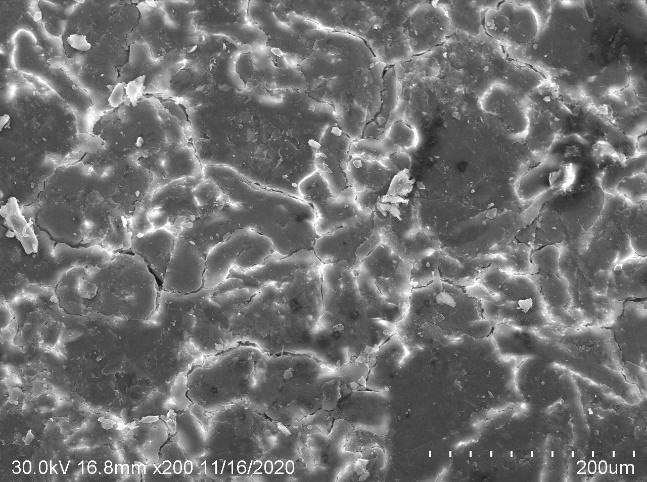

Surface morphology (SEM) analysis

Scanning electron microscopy (SEM) images were studied to determine the morphological changes (surface morphology) of the prepared matrix tablets before and after sintering at 200X magnifications.

SEM (Scanning electron microscopy) micrographs of tablet surface of optimized formulation (both before and after sintering) were shown in fig. 10. SEM micrographs of sintered tablet surface seemed smoother and displayed that a thin film structure covers the tablet surface. This might be due to the fusion of polymer particles due to sintering conditions and uniform redistribution of the polymer in the pores of the tablet.

Fig. 10: SEM micrographs of (A) unsintered (B) sintered tablet surface of optimized formulation